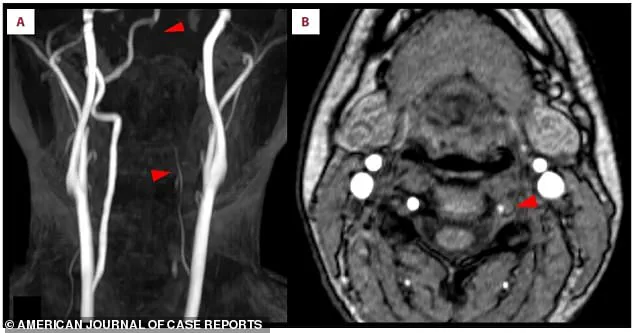

Scan A further revealed that the left vertebral artery, a vital pathway for blood flow to the brain, was thin and faint, suggesting restricted circulation.

Scan B delivered the final confirmation: a crescent-shaped blood clot nestled within the artery’s wall. “That clot was the enemy,” said Dr.

James Carter, the interventional radiologist who performed the thrombectomy. “It was blocking the flow of blood to critical areas of the brain, and every second counted.”